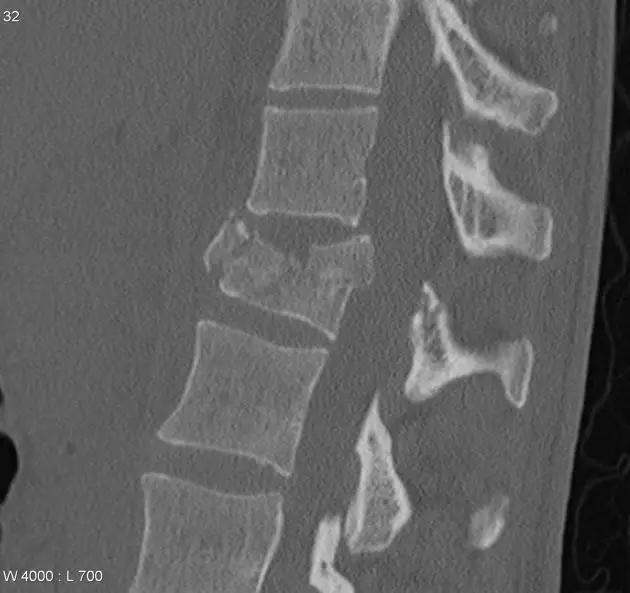

3. Chance 骨折

胸腰段椎体的分离性骨折,伴随脊髓、神经根、椎体的水平方向的崩裂骨折。又称座带骨折(seatbelt fracture)。

由 Chance 于 1948 年首先描述此骨折,故文献又常称 Chance 骨折,为一种屈曲拉伸骨折。典型的损伤机制为汽车座带束于患者腰腹部,当高速行驶的汽车突然减速或撞车时,座带支点以上的躯干屈曲,前冲力还同时产生一个向前拉伸的力量。将椎体由后方向前撕裂,骨折线横过椎体、椎弓根和椎板,椎体后部的韧带完全撕裂。有时前纵韧带亦可撕裂,常合并有神经系统的症状。

(来源:Radiopaedia)